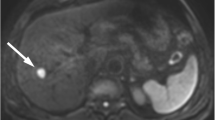

A patient with HCC that was treated with curative resection. The lesion had a low D value. Tumor recurrence occurred 4.67 months after surgery. a Fat-suppressed axial T2WI showing a focal liver lesion with an obvious hyperintense signal. b Axial diffusion-weighted image with a b = 800 s/mm2 shows a hyperintense focal liver lesion. c–f ADC, D, D*, and f pseudocolorized maps showing that the mean ADC, D, D*, and f values of the tumor were 0.817 × 10−3 mm2 /s, 0.709 × 10−3 mm2/s, 5.78 × 10−3 mm2 /s, and 25%, respectively. ADC, apparent diffusion coefficient

A patient with HCC treated with curative resection without recurrence during a follow-up period of 19.75 months. The lesion had a high D value. a Fat-suppressed axial T2WI showing a focal liver lesion with obvious hyperintense signal. b Axial diffusion-weighted image with a b = 800 s/mm2 shows a hyperintense focal liver lesion. c–f ADC, D, D*, and f pseudocolorized maps show that the mean ADC, D, D*, and f values of the tumor were 1.09 × 10−3 mm2/s, 0.994 × 10−3 mm2/s, 20.8 × 10−3 mm2/s, and 18.3%, respectively. ADC, apparent diffusion coefficient